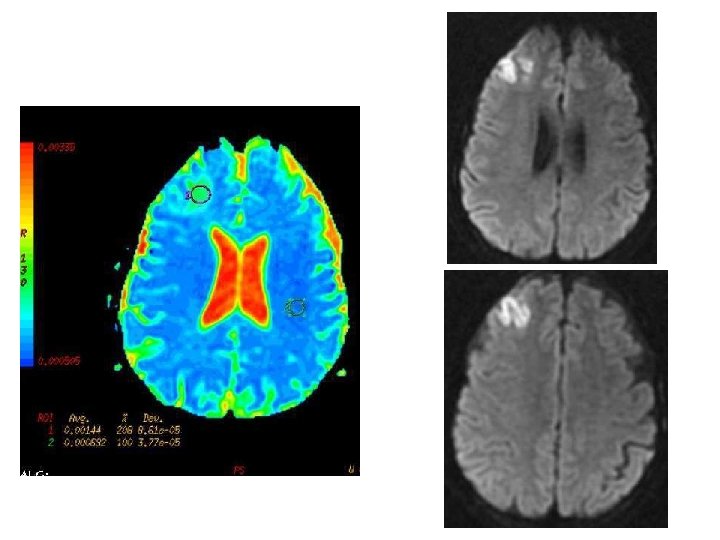

IRM de diffusion • Infarctus veineux – valeurs d ’ADC hétérogènes – œdème vasogénique ( AVC artériel) • +/- Thrombus en hypersignal Intérêt pronostic ? Favrolle et al, Stroke 03 57